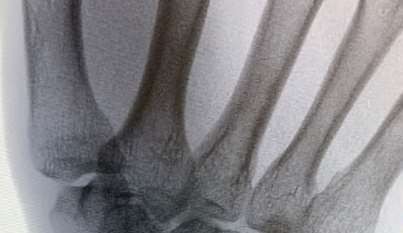

A 35-year-old woman reports wrist pain after a fall onto an outstretched hand. On exam, she has focal tenderness over the wrist snuffbox. A radiograph and CT image are shown in Figures A and B. What is the proper treatment of her injury?